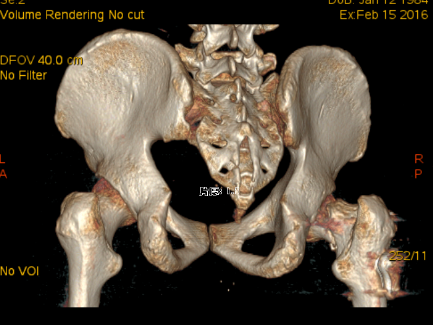

术后三维CT成像

在医生为病人解除病痛,救死扶伤的背后,是技术创新、工具升级所提供的推动力。3D打印技术近年来在国内医疗领域探索应用前景被普遍看好,特别是骨科专业。我院骨科走进医疗领域前列,2015年12月首次在骨科手术中使用3D打印技术指导股骨颈骨折切开复位内固定术,为骨科3D技术打开了新局面。随后对创伤骨科及关节骨科中复杂的骨折均术前进行CT扫描后进行3D打印成型,让手术医生能在术前直观了解到骨折的类型,术前进行骨折手术复位指导,从而增加了手术的精确性,实现了骨科手术私人定制,3D打印技术逐渐应用到骨科各个部位,拓展了我院骨科技术新领域,再次成为行业先进。

2015年12月,一名32岁的青年男性工作时不慎从高处坠落导致股骨颈骨折(经颈型)而入住我院骨创伤与手外科,考虑该类骨折具有很高的坏死率,患者越年轻坏死率越高。“以往,该类骨折手术的实施主要依靠患者的X光片进行手术分型,但X光片的缺陷主要在于其平面化,因此往往需要医生有一个立体空间的想象力,才能为接下来的手术做好铺垫。”即使行局部骨折三维重建也难以让手术医师有个直观的感觉,无法在体外对其进行术前预演。因患者体重较肥胖,骨折移位明显,为降低患者的股骨头坏死率的发生,科室主任陈跃平教授提出使用3D打印技术的“提前干预”,通过3D打印出他的全仿真患者股骨颈进行手术预演,因为有了预演的经验,最终手术得以精准、迅速完成,耗时较以往少了一半以上,目前创伤骨科已为近10位患者成功实施手术,患者术后恢复良好。